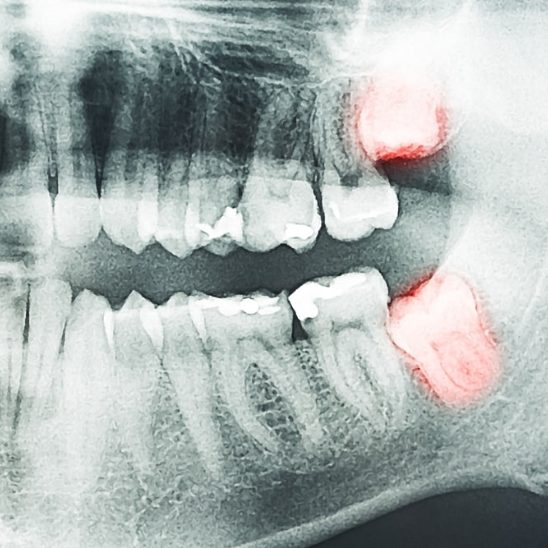

- Les dents de sagesse : ces grosses dents poussent parfois de façon irrégulière, faute d’espace suffisant. Pour cette raison et leur positionnement au fond de la bouche, elles sont plus à risque de développer des pathologies (caries, abcès, infections gingivales, kystes, tumeurs) ;

Les dents de sagesse sont susceptibles de développer des maladies, comme des kystes, et elles représentent un risque possible pour leurs dents adjacentes. C’est notamment le cas si elles sont mal positionnées, semi-incluses ou incluses (elles sont sorties en partie ou pas du tout). Elles sont alors plus vulnérables aux bactéries qui pourraient aussi attaquer les tissus avoisinants. De plus, elles peuvent nuire à la racine des dents qui les entourent.

- Elles peuvent être retirées avant même leur éruption

On peut procéder à une extraction préventive dès la fin de l’adolescence. La dentiste évaluera d’abord la situation et, si elle suspecte une malposition ou une éruption irrégulière, elle proposera la chirurgie. Celle-ci est d’ailleurs plus facile à réaliser à ce moment, vu la plasticité de la mâchoire. Si on juge que ces dents ne posent pas problème, on pourra les laisser en place.